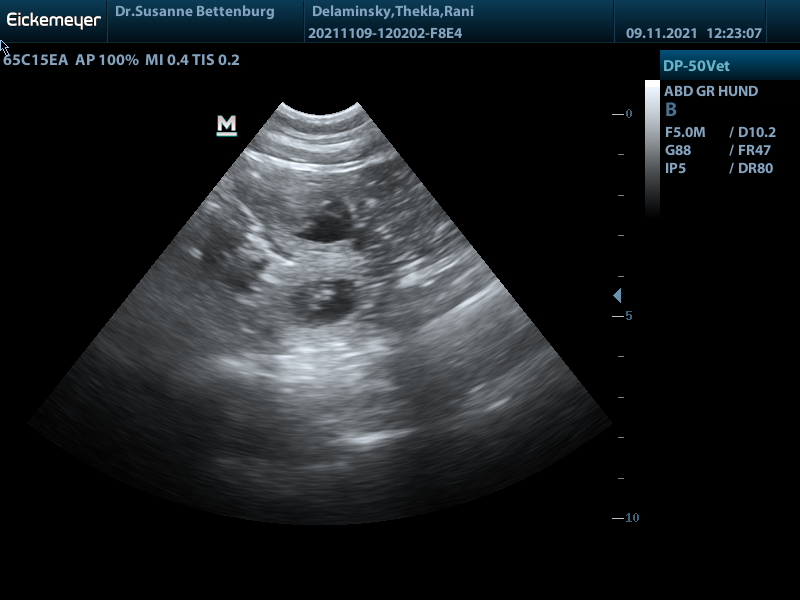

Ultraschall vom 09.11.2021: Hurra Rani ist tragend!